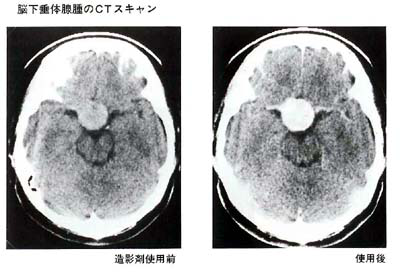

(2)CT掃描

研究垂體周圍的骨骼變化,只是間接診斷。另一方面,由于CT掃描可以使腫瘤本身可視化,因此可以知道腫瘤確切的大小和范圍。在注射造影劑之前和之后檢查兩次以確定差異。在這種情況下,某些人很少會(huì)出現(xiàn)造影劑引起的過(guò)敏癥狀,例如蕁麻疹。